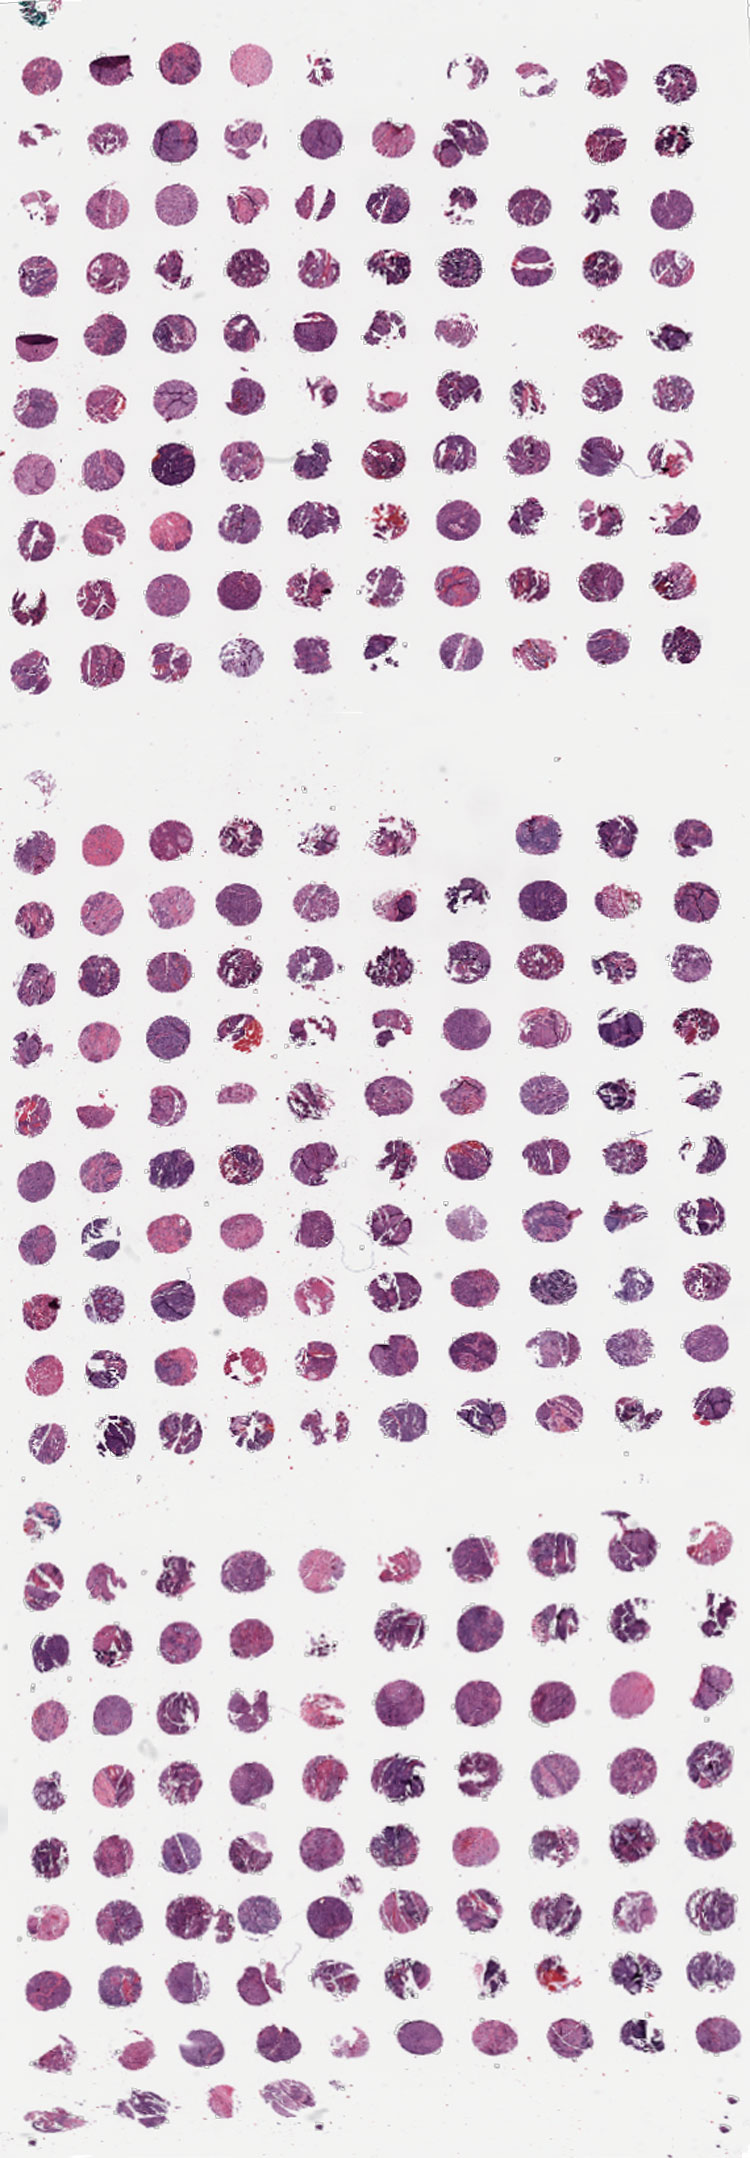

TMA 20 - 9811

Click on below images to enlarge.

TMA 20 - 1

TMA 20 - 2

TMA 20 - 3